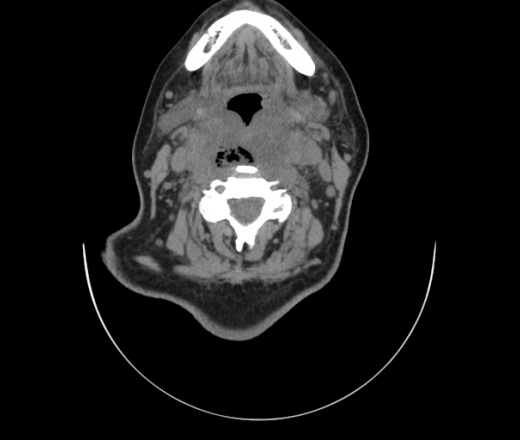

Женщина поступила в х/о спустя 4 дня после того как при употреблении карася подавилась костью.

Наличие газа в средостении на протяжении тел С2-С6 (медиастинальна эмфизема); рыбная кость на уровне тела С6.

При всем уважении, но говорить о медиастинальной эмфиземе, оценивая мягкие ткани шеи, как-то слишком резко. На мой взгляд, это ретрофарингеальное пространство.

Эвакуировали почти 100мл гноя. Но кость не смогли найти. Думаю что она даст дальнейшее ослоднение. Эндоскопически за черпалонадгортаной звязкой не смогли зайти в пищевод, все мягкие ткани отечные, просвет пищевода сдавлен. По всей видимости параэзофагеальная клетчака тоже задействована. Эмпиема, если ее можно так назвать, незнаю как правильно дошла до уровня яремной вырезки. Чем закончиться напишу. Ждем медиастинита.

Флегмона заглоточного пространства шеи, только операция, флегмоны вскрывают. Риск медиастинита.

Согласен с Вами; конечно, наличие газа в клетчатке ретрофарингеального пространства (затмение с опечаткой..). К сожалению, процесс "продвигается" к медиастиниту. Но почему никто, не отмечает наличие рыб. кости; или это для Всех очевидно?

Так вы уже отметили. Хотя ориентировал бы не скелетотопически, а на перстнечерпаловидный сустав.

Кость то мы сразу выявили, размеры где то 17*2мм, но ее так и не получается найти в этой каше